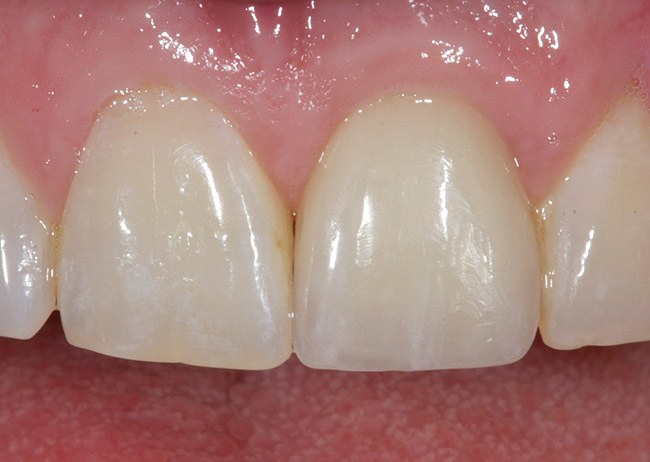

Preoperative photograph.

Figure 11

Postoperative photograph of patient shown in Fig 11 after immediate implant placement with immediate loading, tooth No. 9.

Figure 12

Achieving outstanding esthetics with implant dentistry is a reality (Figure 11 and Figure 12). Restorative efforts require disciplined steps to attain predictable results. To paraphrase my mentor, Cary Shapoff, DDS, renowned for his knowledge of periodontal disease treatment, bone grafting procedures, and dental implant surgery, implant esthetics is a series of well-planned, well-executed small steps that add up to a successfully restored fixture.